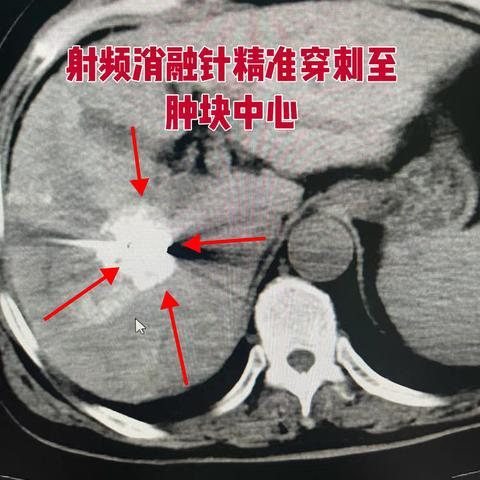

射频消融肿瘤君,让“瘤”细胞无处可留